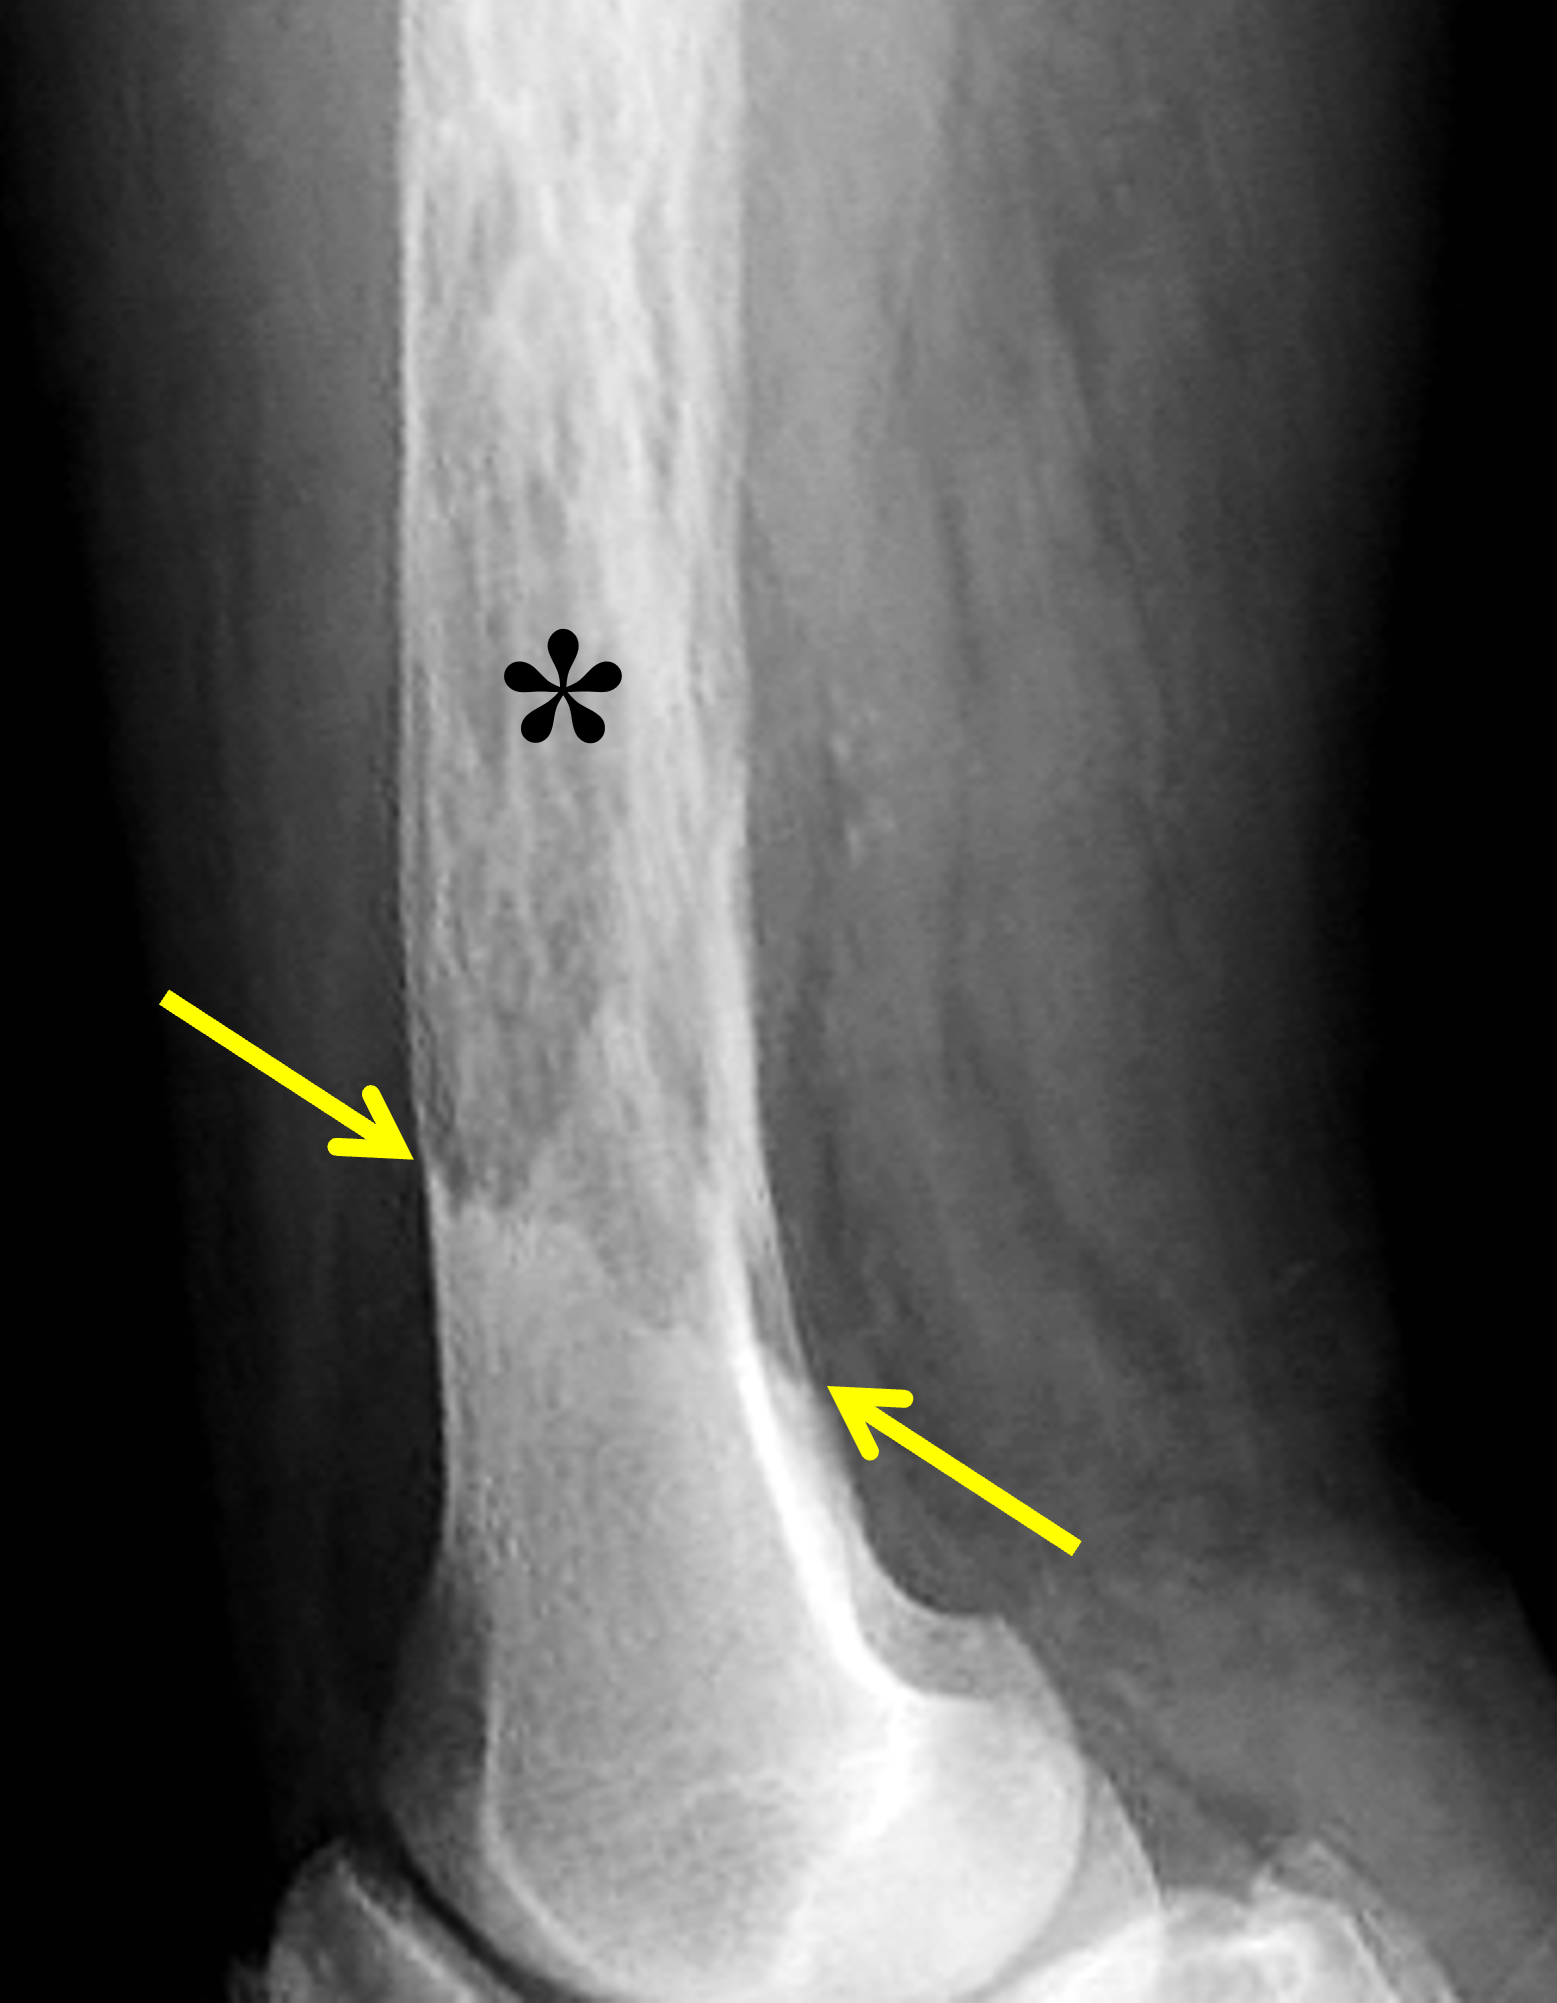

Figure 6: Lytic to early mixed phase Paget disease of the distal femur. (6A) Lateral radiograph shows extensive osteolysis and coarse trabeculae in the femoral shaft (asterisk). It is often difficult to confidently identify thickened cortex during the active phase of osteolysis. Note the sharp transition from Pagetoid bone to normal bone distally (between arrows). (6B) Axial fat-suppressed, fluid-sensitive image demonstrates mildly thickened cortex containing tubular areas of very high signal intensity (arrows), suggesting dilated vascular channels.